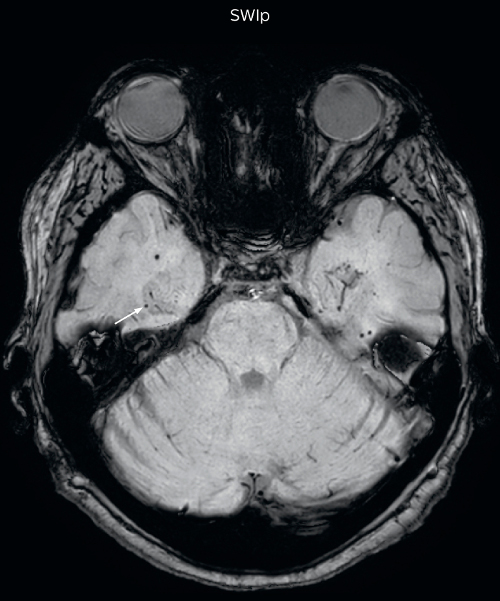

Gradient echo imaging and SWIp are compared in a patient with radiation-induced foci of hemosiderin deposition. A greater number of small foci is seen on the SWIp image. Ingenia 3.0T